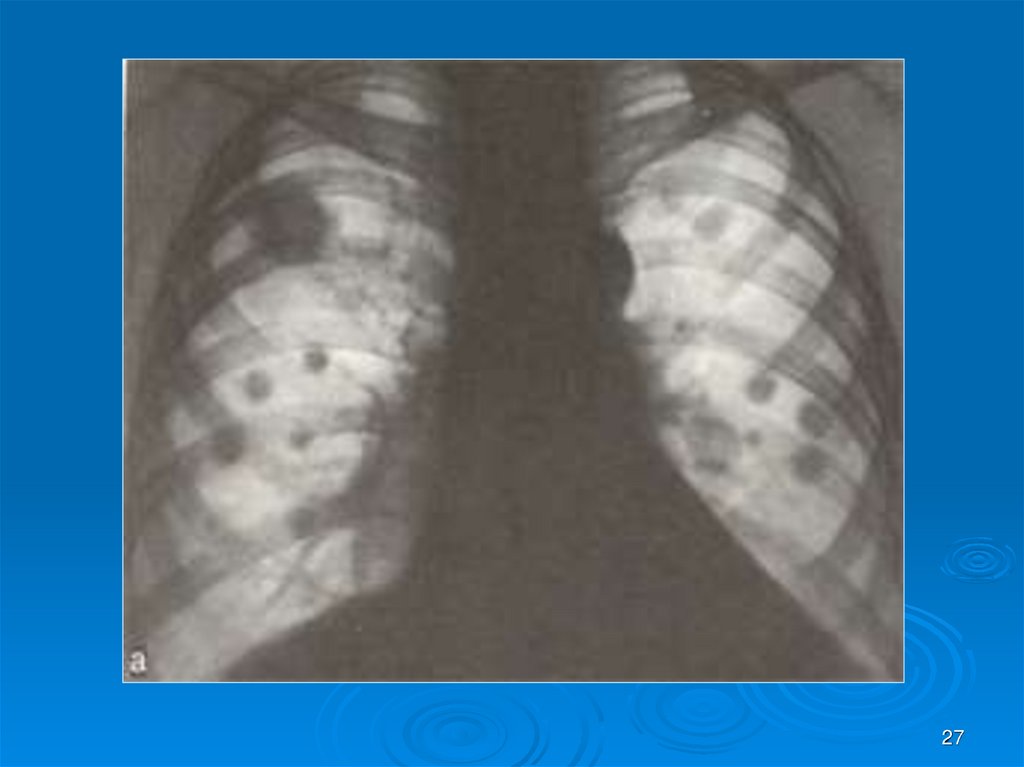

27.

27